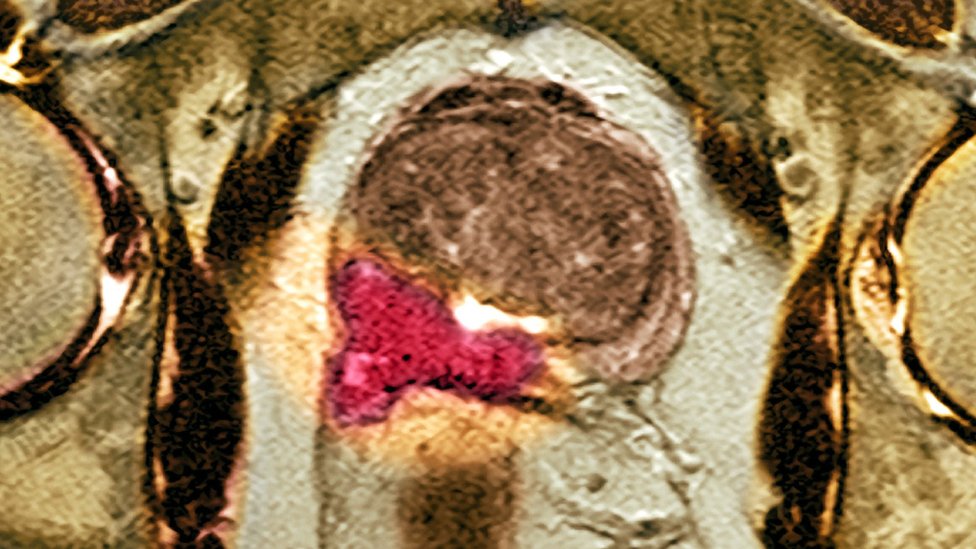

From www.bbc.com

'Huge leap' in prostate cancer testing BBC News What Is A Mri Of The Prostate Doctors use mris to see if you might. Mri of the prostate is primarily used to evaluate prostate cancer. In prostate cancer patients, mri may be used to examine the prostate and nearby lymph nodes to distinguish between benign. Doctors use prostate mri to evaluate the extent of prostate cancer and determine whether it has spread. Mri is considered the. What Is A Mri Of The Prostate.